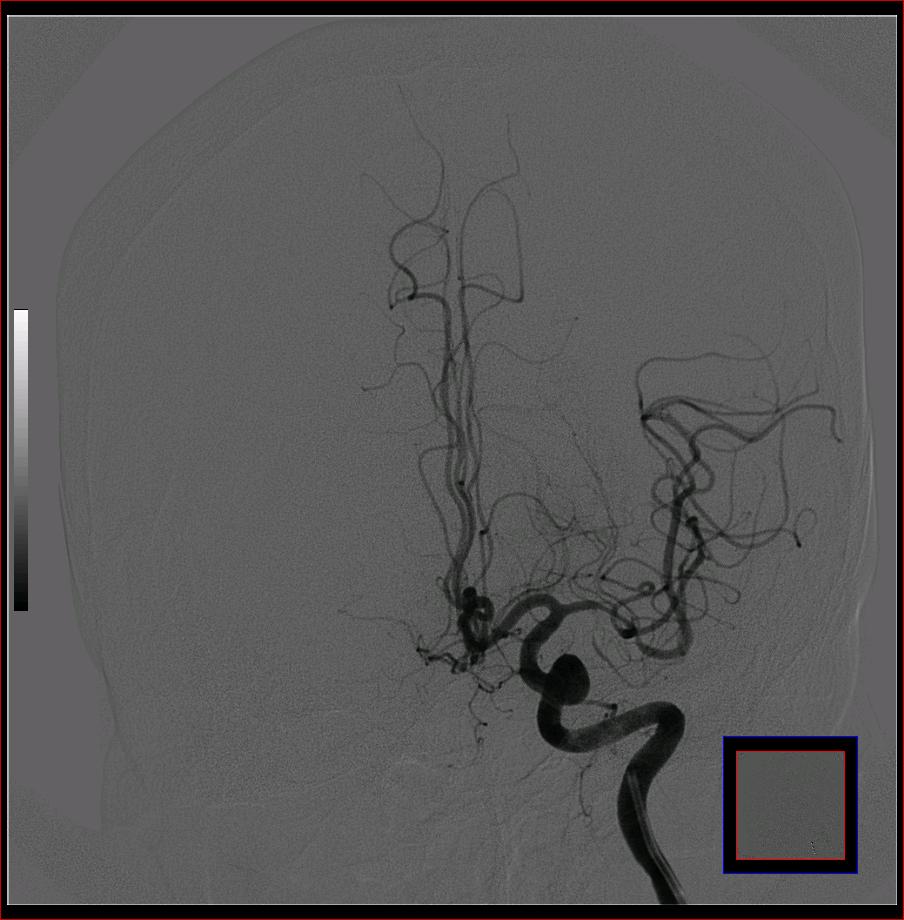

标题: DSA0121:脑血管造影

男,65岁,肢体无力。

左侧大脑中动脉水平段狭窄.

右侧大脑前a缺如.左侧大脑中动脉m1段狭窄,远端分支分布稀疏.

前交通或稍远端动脉瘤要仔细查,左大脑中动脉狭窄要鉴别,有可能是痉挛,因为造影导管插得稍深啦。其它就是供血动脉变异较大

烟雾病